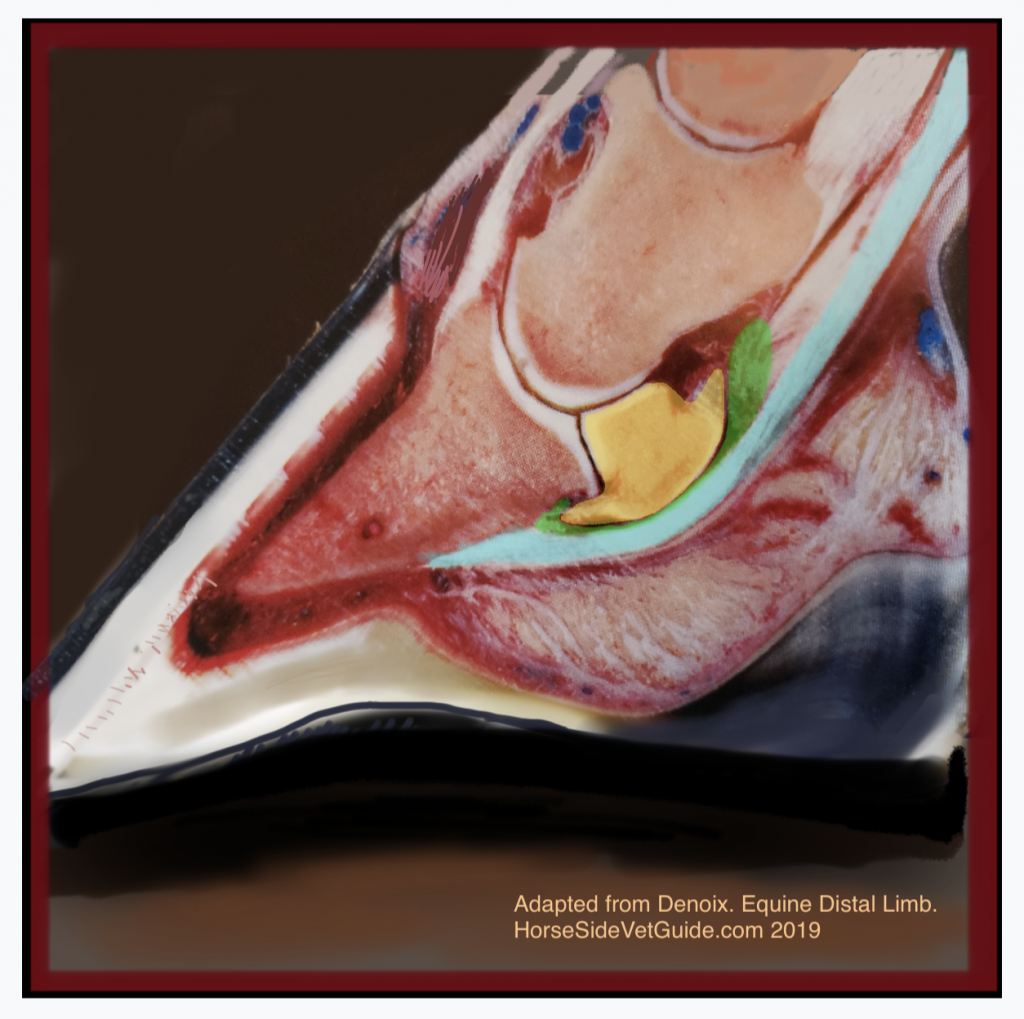

Superficial Digital Flexor (SDF) Tendinitis | HorseDVM Diseases A-Z

Callie’s Deep Digital Flexor Tendon (‘Bowed Tendon’) Injury | HorseDVM

Callie’s Deep Digital Flexor Tendon (‘Bowed Tendon’) Injury | HorseDVM

Callie’s Deep Digital Flexor Tendon (‘Bowed Tendon’) Injury | HorseDVM

Callie’s Deep Digital Flexor Tendon (‘Bowed Tendon’) Injury | HorseDVM

Callie’s Deep Digital Flexor Tendon (‘Bowed Tendon’) Injury | HorseDVM

Callie’s Deep Digital Flexor Tendon (‘Bowed Tendon’) Injury | HorseDVM

Ligaments and tendons of the distal digit in the horse. | Horse care …

Callie’s Deep Digital Flexor Tendon (‘Bowed Tendon’) Injury | HorseDVM

Callie’s Deep Digital Flexor Tendon (‘Bowed Tendon’) Injury | HorseDVM

Solar Insertion of Deep Digital Flexor Tendon in Equine | Horse health …

Callie’s Deep Digital Flexor Tendon (‘Bowed Tendon’) Injury | HorseDVM

Callie’s Deep Digital Flexor Tendon (‘Bowed Tendon’) Injury | HorseDVM

Callie’s Deep Digital Flexor Tendon (‘Bowed Tendon’) Injury | HorseDVM